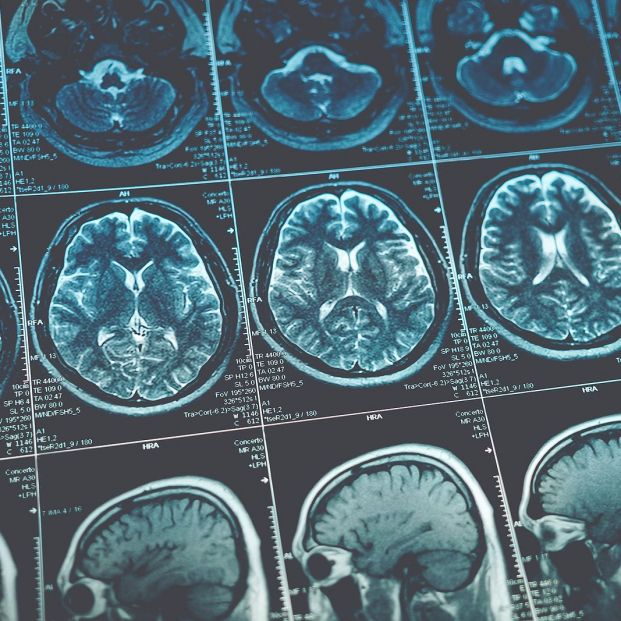

La Fundación Pasqual Maragall ha concedido una beca a un proyecto de investigación centrado en el estudio de las fases iniciales de la enfermedad de Alzheimer, liderado por la Dra. Amayra Hernández-Vega, investigadora del Instituto de Bioingeniería de Cataluña (IBEC).

La investigación analiza los cambios iniciales de la proteína tau, "clave en la estructura neuronal", cuando comienza a modificar su comportamiento y a formar agregados patológicos, para identificar los mecanismos que desencadenan la enfermedad.

Se realizará junto a la Dra. Natalia Rodríguez-Muela, del Centro Alemán de Enfermedades Neurodegenerativas (DZNE), y combinará modelos in vitro y humanos de alzhéimer familiar para identificar factores asociados a la edad y "posibles inhibidores" que frenen la progresión primeriza.